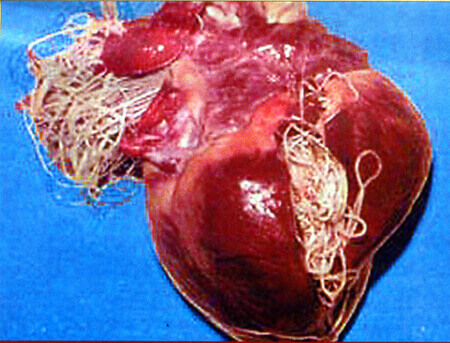

Además, pueden incluso destruir un cuerpo que parece joven y saludable. Yo diría que las muertes causadas por parásitos representan el 85 % de todas las muertes inesperadas o llamadas "súbitas". Mire estas fotos realizadas en nuestro laboratorio:

Hay parásitos dentro del corazón de una mujer de 45 años. La presencia de parásitos no se descubrió hasta después de su muerte:

Los parásitos en el corazón de la mujer de 45 años de edad que fueron encontrado después de su muerte: